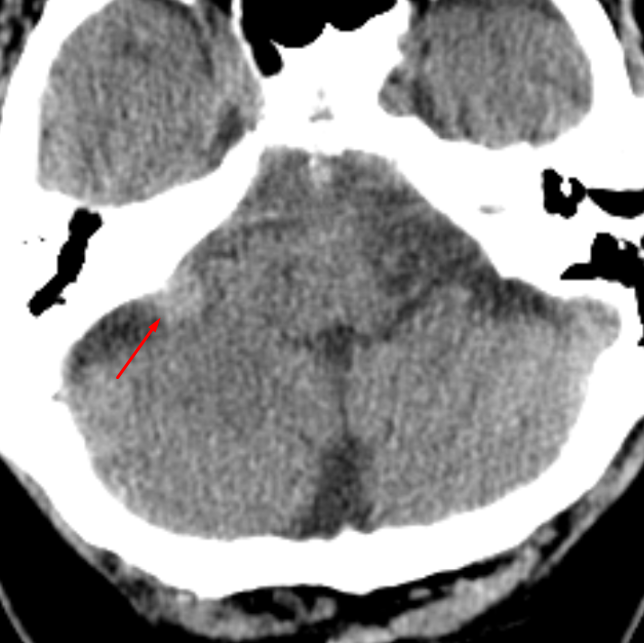

Age: 50

Sex: Female

Indication: Headache